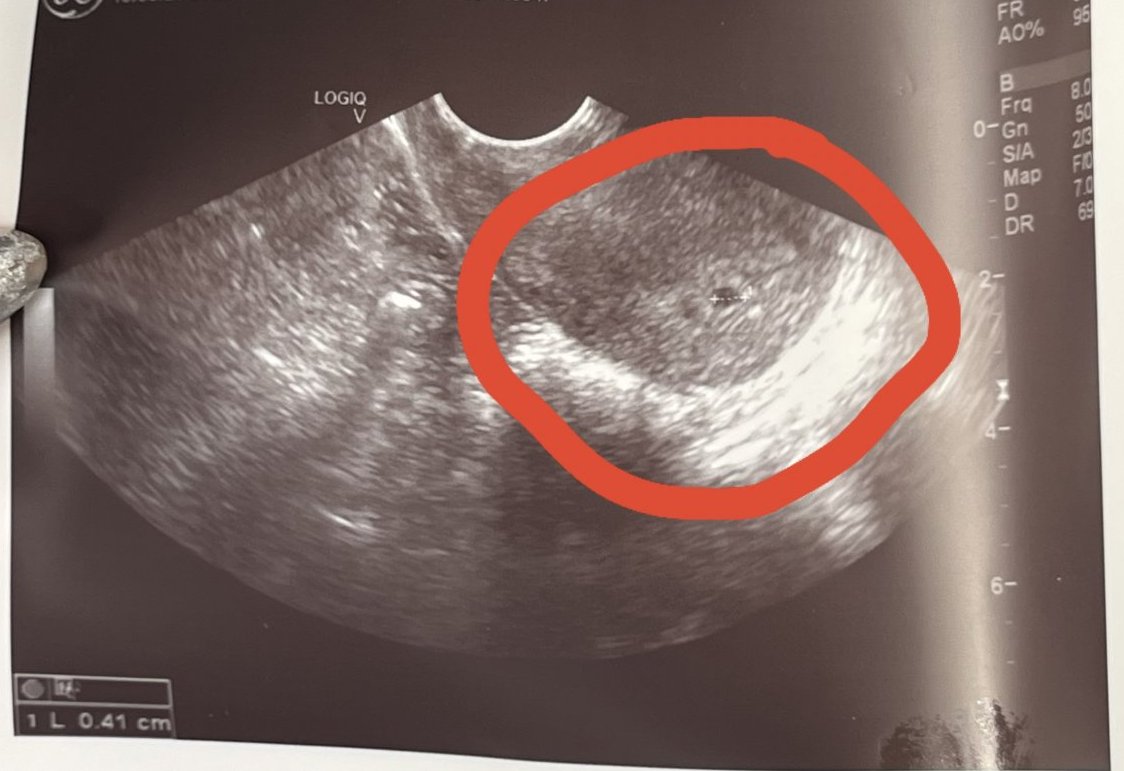

Какво представляват белите точки в плодния сак на ехографската снимка?

Какво представляват черните точки в матката на ехографската снимка?